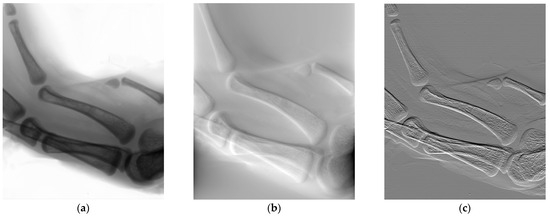

3.4. Large Field of View